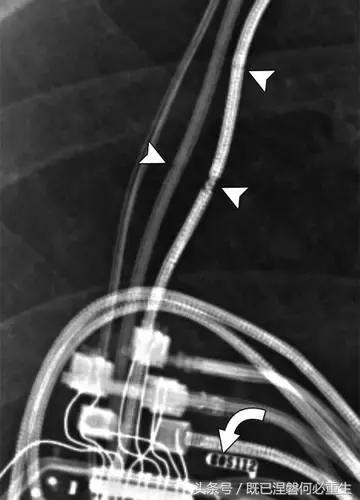

图。 7A 79岁的男性患有电极折断和迁移。

A,初始胸前X线片显示Pacesetter双腔起搏器低于锁骨的心房导线不完全断裂(变薄)(箭头)。

图。 7B 79岁的男性患有电极折断和迁移。

B,大约3年后,电极完全断裂,金属传导碎片(箭头)分离。 远端片段(箭头)已经偏移尾侧,但是由于围绕电极的射线可穿透鞘的约束效应而没有迁移到肺循环中。 引线和中心静脉导管最常见于锁骨和第一肋骨之间断裂,因为它们在臂运动期间被锁骨下肌肉或腱或肋锁韧带压缩[16]。

造成设备故障的最常见的X光检查原因之一是铅断裂。锁骨下静脉经过锁骨下的部位是骨折最常见的位置[16](图7A和7B)。在这个位置的损伤可能发生在导管或导线,并已被描述为锁骨下夹断综合征和锁骨下压溃综合征[16?18]。临床上,骨折的导线通常在患者中产生可以是连续的,间歇的或依赖于患者定位的症状。识别这些状况可能需要挑衅性的动作,例如等长臂锻炼,仰卧或侧向定位或Valsalva。设备检查将显示异常的起搏阻抗(如果绝缘破裂允许导体暴露则减小,如果导体断裂但绝缘完好则增加),感测错误和起搏捕获损失[12]。导线断裂或绝缘损坏可能导致感测或起搏异常。对心律失常的不适当的过感知或欠感应可能导致不适当的治疗,例如抗心动过速起搏和休克治疗,或不适当的抑制治疗。